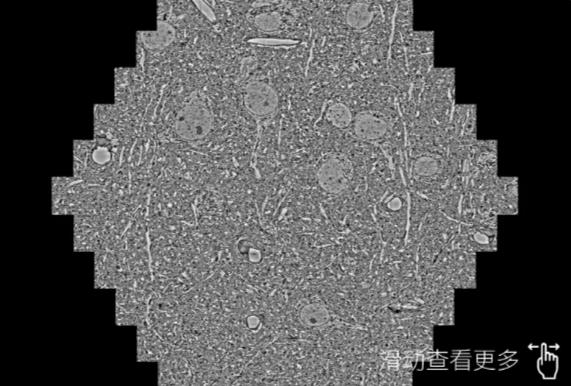

鼠脑切片。左图使用内蒙古蔡司内蒙古扫描电镜MultiSEM706对165μmx143pm面积区域成像,耗时仅需1.5秒。右图为鼠脑切片中30μm区域放大效果。样品由芝加哥大学B.Kasthuri提供。

使用蔡司高速内蒙古扫描电镜MultiSEM对1mm²人脑皮层组织进行高分辨成像,并对其中的各种细胞结构进行三维重构分析。左图展示了2x3mm²组织平面中锥体神经元的三维重构效果。右图显示了局部体积神经元三维重构。图像由哈佛大学chtman实验室提供,渲染图由D. Berger 制作。